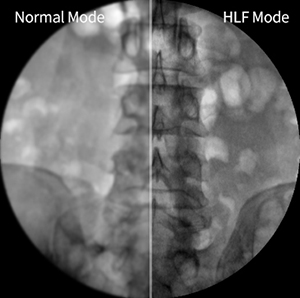

High-Level Fluoroscopy Mode

HLF Mode

High Powered HLF Mode produces high quality image with its uncomparable fluoroscopy and penetration than other standard C-Arms.